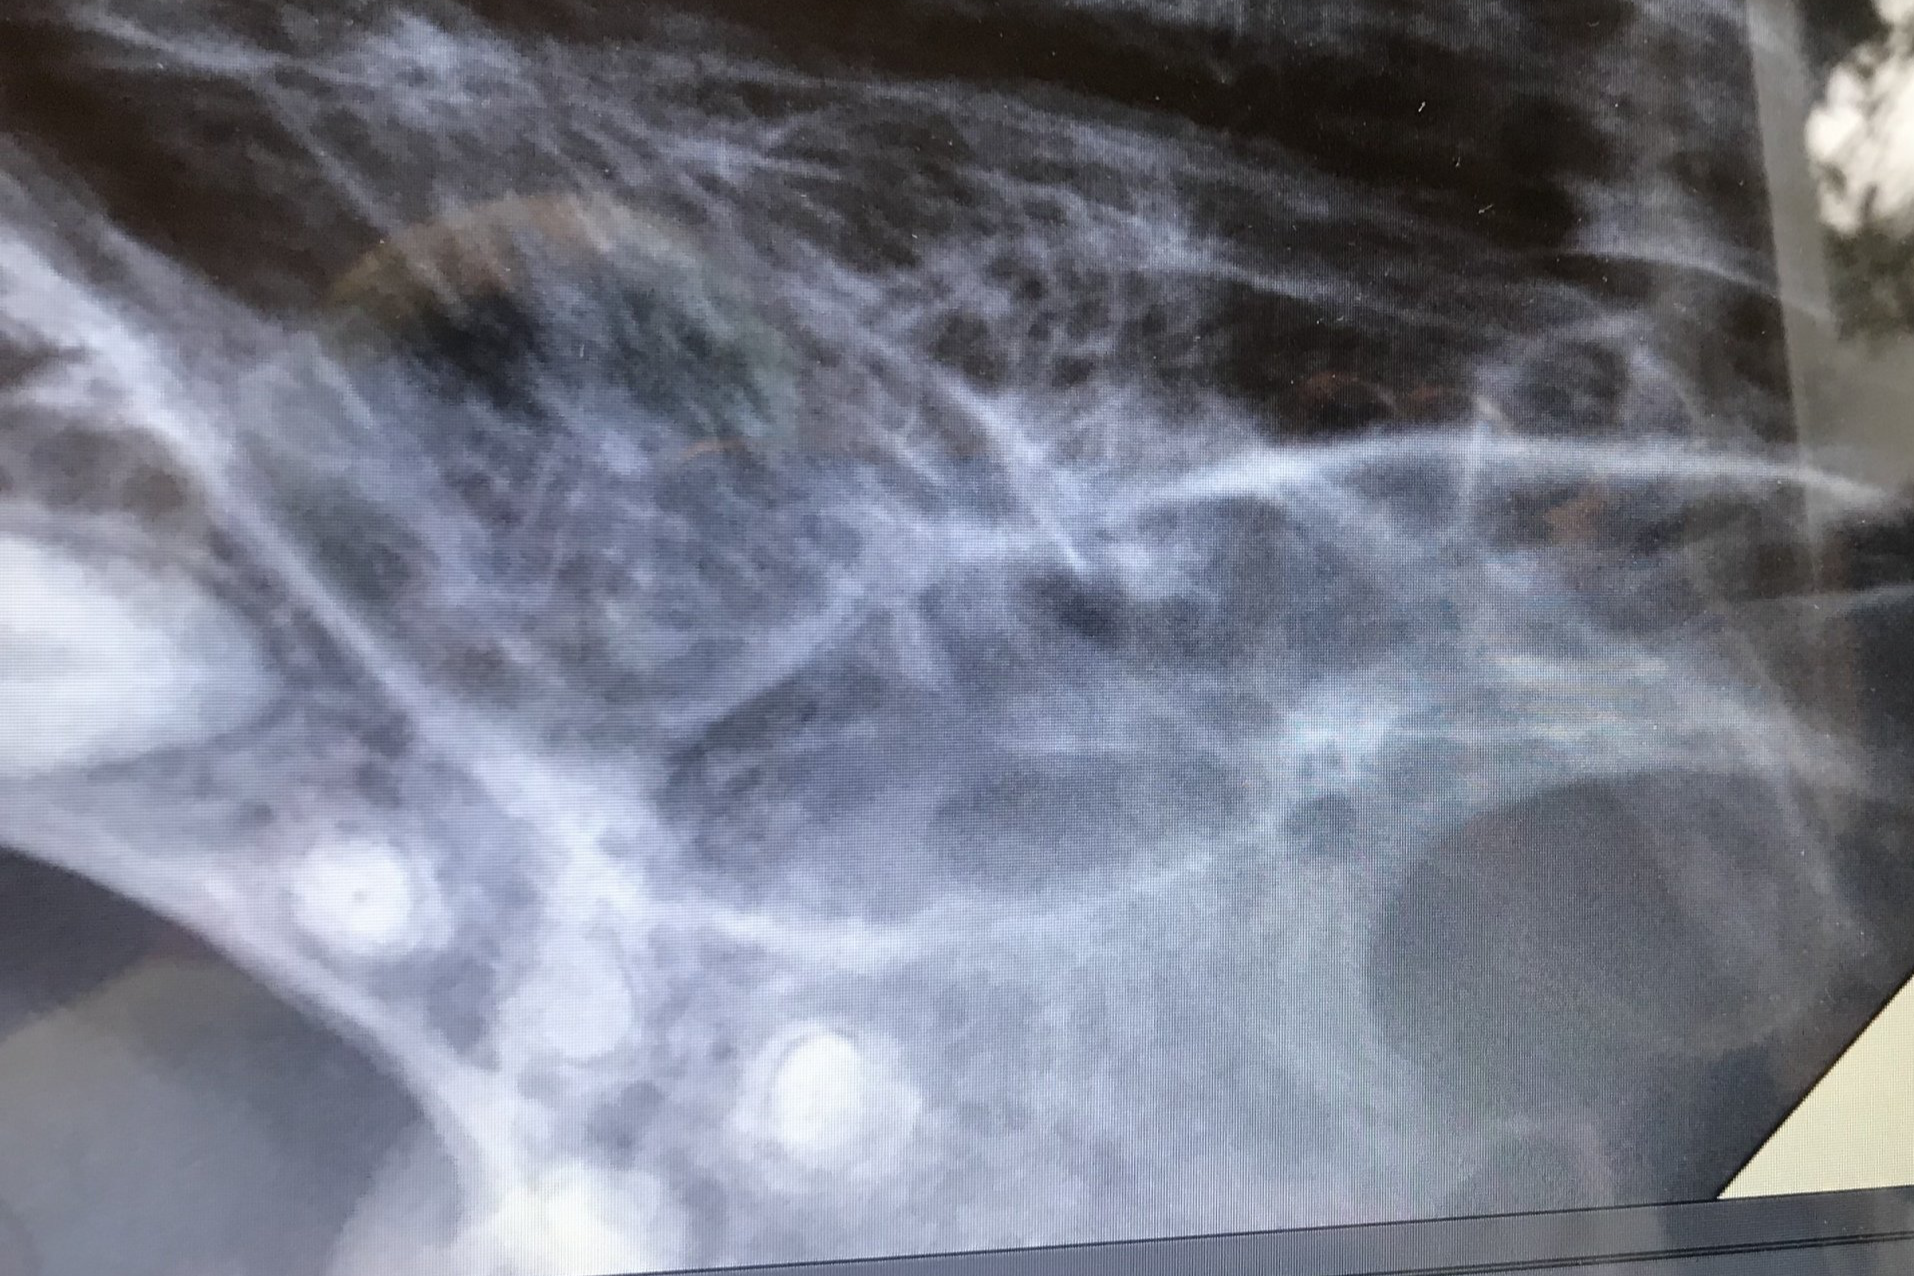

Een hond met ernstige Parodontitis

Op foto 1 en 4

zie je de kiezen in de kaak, ogenschijnlijk nog mooie elementen om te zien, maar

Op foto 2 en 5

zie je de röntgenfoto's van deze kiezen. Opvallend is de grote hoeveelheid verlies van kaakbot rondom eigenlijk alle wortels (verticaal botverlies) en ook het verlies van bot in de splitsing van de wortels (de bifurcatie) en tussen de verschillende kiezen (horizontaal botverlies) Botverlies zie je op een röntgenfoto aan het minder wit zijn van het bot (rond de wortels). Normaal sluit het bot veel hoger aan tegen de wortels en je ziet ook zwarte ruimtes onder de elementen, het bot hoort tot bovenin aan te sluiten.